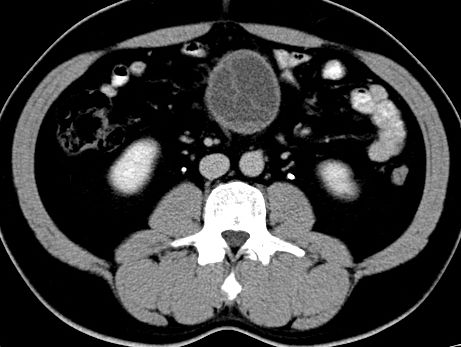

(腹腔)神经鞘瘤

男,48岁,间断性下腹不适1年。

手术探查

:距回盲部28厘米处肠系膜根部可见5*7cm左右包块,质中等硬度,活动度尚可,肝、胆、胰、脾肾未见明显异常。

病理

:(腹腔)

神经鞘瘤

,伴出血、坏死及囊性变,伴淋巴结反应性增生。

免疫组化结果

:sma(-), desmin(-), cd117(-), s-100(+++), nf(-),vimentin(+++).